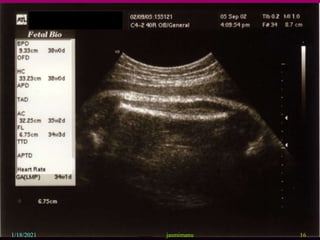

This document provides information about intrauterine growth restriction (IUGR), including its definition, classification, etiology, diagnosis, treatment and risks. IUGR occurs when a baby's growth is slowed or restricted during pregnancy. It can be symmetric, affecting overall growth, or asymmetric, affecting the growth of some parts more than others. The causes of IUGR are often unknown but can include maternal, fetal, placental or genetic factors. Diagnosis involves assessing growth via ultrasound and monitoring blood flow. Treatment may involve bed rest, aspirin or early delivery depending on gestational age and fetal wellbeing. Both short and long term risks to the infant are increased with IUGR.